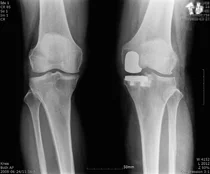

연세사랑병원, 줄기세포와 인공관절 등 다양한 관절염 치료 제공

우리나라가 초고령화 사회로 진입하면서 암과 당뇨병 등 중증질환 뿐 아니라 무릎과 손발 등 퇴행성관절염 환자가 급증하고 있어 삶의 질 향상을 위해 선제적 관리가 필요하다는 지적이 나오고 있다.

연세사랑병원, 증강현실 이용 무릎 인공관절 수술 프로그램 개발

보건복지부 지정 관절전문 연세사랑병원은 아산병원, 의료기기업체 스카이브 연구팀과 함께 미국 캘리포니아에서 열린 미국정형외과연구학회(ORS)에서 ‘인공지능(AI)을 이용한 소아에서 슬개골 아탈구에 대한 위험요소’를...

연세사랑병원, 모션 캡쳐 도입..인공관절 수술 환자 ‘관절 기능 정상화’ 도와

연세사랑병원은 인공관절 수술 환자의 관절 기능 회복을 도모하기 위해 모션캡쳐(동작분석) 기계를 도입했다고 23일 밝혔다. 연세사랑병원은 지난해 8월 신축확장이전을 통해 전반적인 병원 시설을 업그레이드했다.

스카이브·연세사랑병원 개발 ‘인공관절 수술기구’ 신의료기술 신청

기술혁신형 이노비즈(Inno-Biz) 벤처기업 스카이브는 연세사랑병원과 공동 개발한 인공관절 수술기구(PSI) 제품에 대한 신의료기술 신청을 완료했다고 12일 밝혔다.

한국형 인공관절 수술 후, 간호간병 통합서비스로 환자 부담 줄일 수 있어

퇴행성관절염은 뼈와 뼈 사이에서 하중 부담과 완충 역할을 하는 연골이 노화나 과도한 사용으로 인해 닳아 염증과 통증이 발생하는 질환이다. 고령화 사회에서 흔히 발생하는 질환 중 하나로 초기 치료가 중요하다.

자기관절 보존하는 ‘인공관절 부분치환술’...정밀한 삽입 위치 선정 중요

퇴행성관절염은 65세 이상 노령층에서 흔하게 발생하는 질병이다. 주로 노령층에서 발병하지만 중년 이후부터는 특별한 외상이 없어도 관절이 붓고 아픈 증상이 있다면 의심할 필요가 있다.